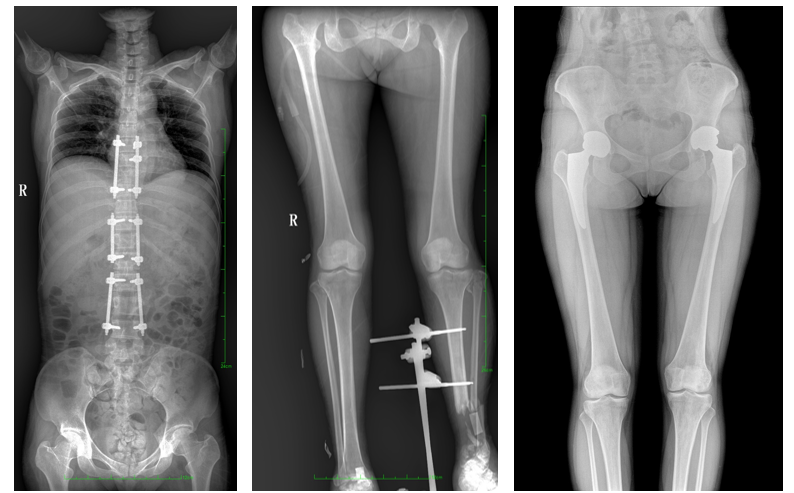

一、成像面积大。17"*34"有效视野,一次成像不拼接。相较于多张摄影再软件拼接的DR设备,大视野平板动态DR解决了拼接图像存在密度不均匀,拼接处图像配准和放大效应等问题,给临床带来了大视野影像解决方案,可一次性覆盖全脊柱或双下肢影像。

PLX8600大视野平板动态DR可在低辐射剂量下获得患者站立位、卧位的高质量影像。搭载自主研发的图像均衡处理系统,能够很好的均衡人体不同厚度组织的影像,视野大,图像清晰,层次丰富。